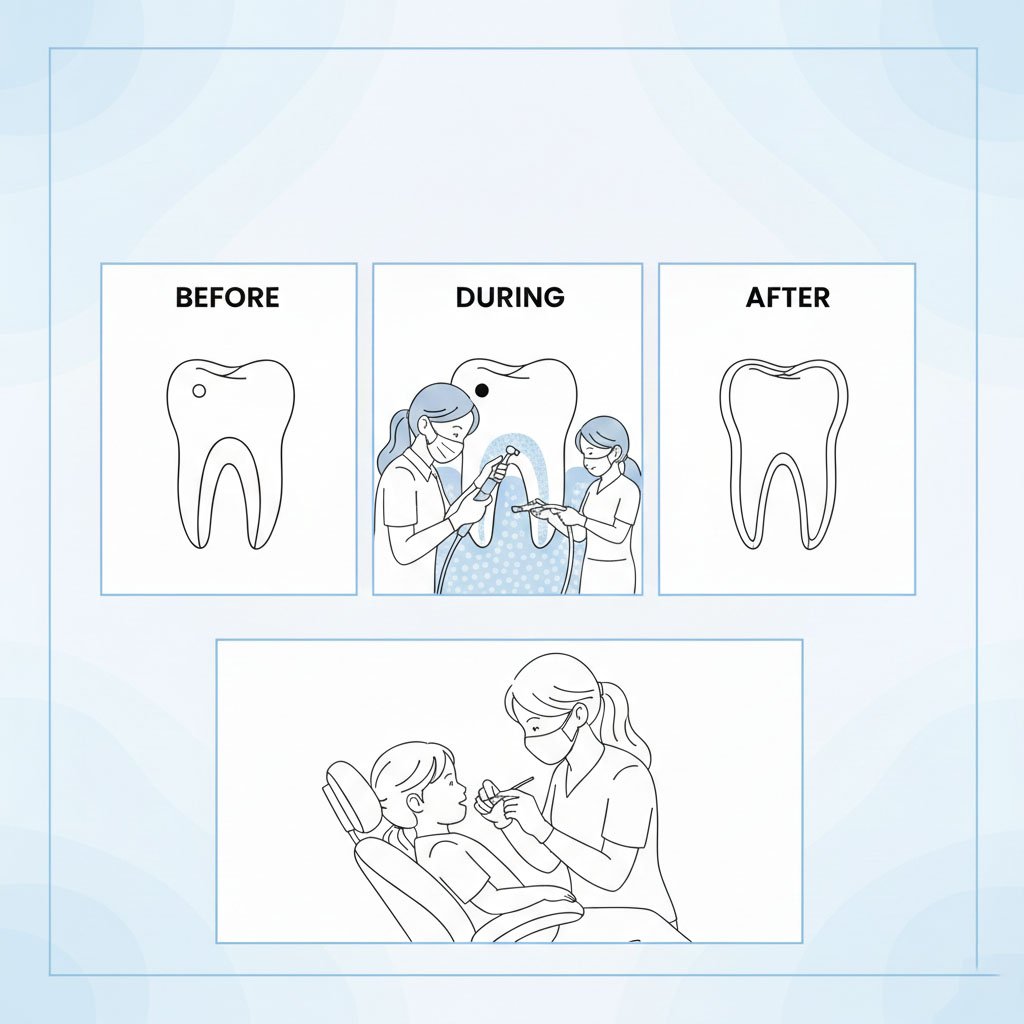

Pain-Free Single Sitting RCTs